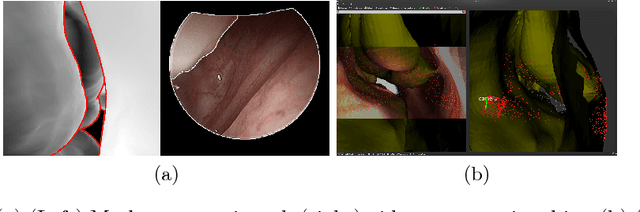

Abstract:Functional endoscopic sinus surgery (FESS) is a surgical procedure used to treat acute cases of sinusitis and other sinus diseases. FESS is fast becoming the preferred choice of treatment due to its minimally invasive nature. However, due to the limited field of view of the endoscope, surgeons rely on navigation systems to guide them within the nasal cavity. State of the art navigation systems report registration accuracy of over 1mm, which is large compared to the size of the nasal airways. We present an anatomically constrained video-CT registration algorithm that incorporates multiple video features. Our algorithm is robust in the presence of outliers. We also test our algorithm on simulated and in-vivo data, and test its accuracy against degrading initializations.